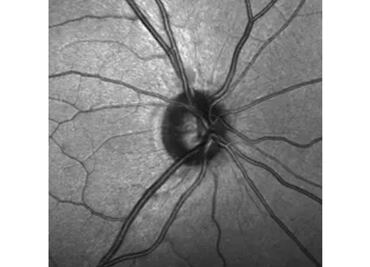

El glaucoma daña progresivamente el nervio óptico, afectando la visión sin síntomas tempranos. Revisa tus ojos a tiempo.

El glaucoma se presenta cada vez a edades más tempranas

Se trata de una afección con la que se va disminuyendo la visión de forma gradual

Sin estas células, el nervio es incapaz de repararse a sí mismo de los daños causados por el glaucoma

En el mundo hay 3 millones de personas ciegas debido a este mal; en el país, 4% de los mayores de 40 años padecen la enfermedad